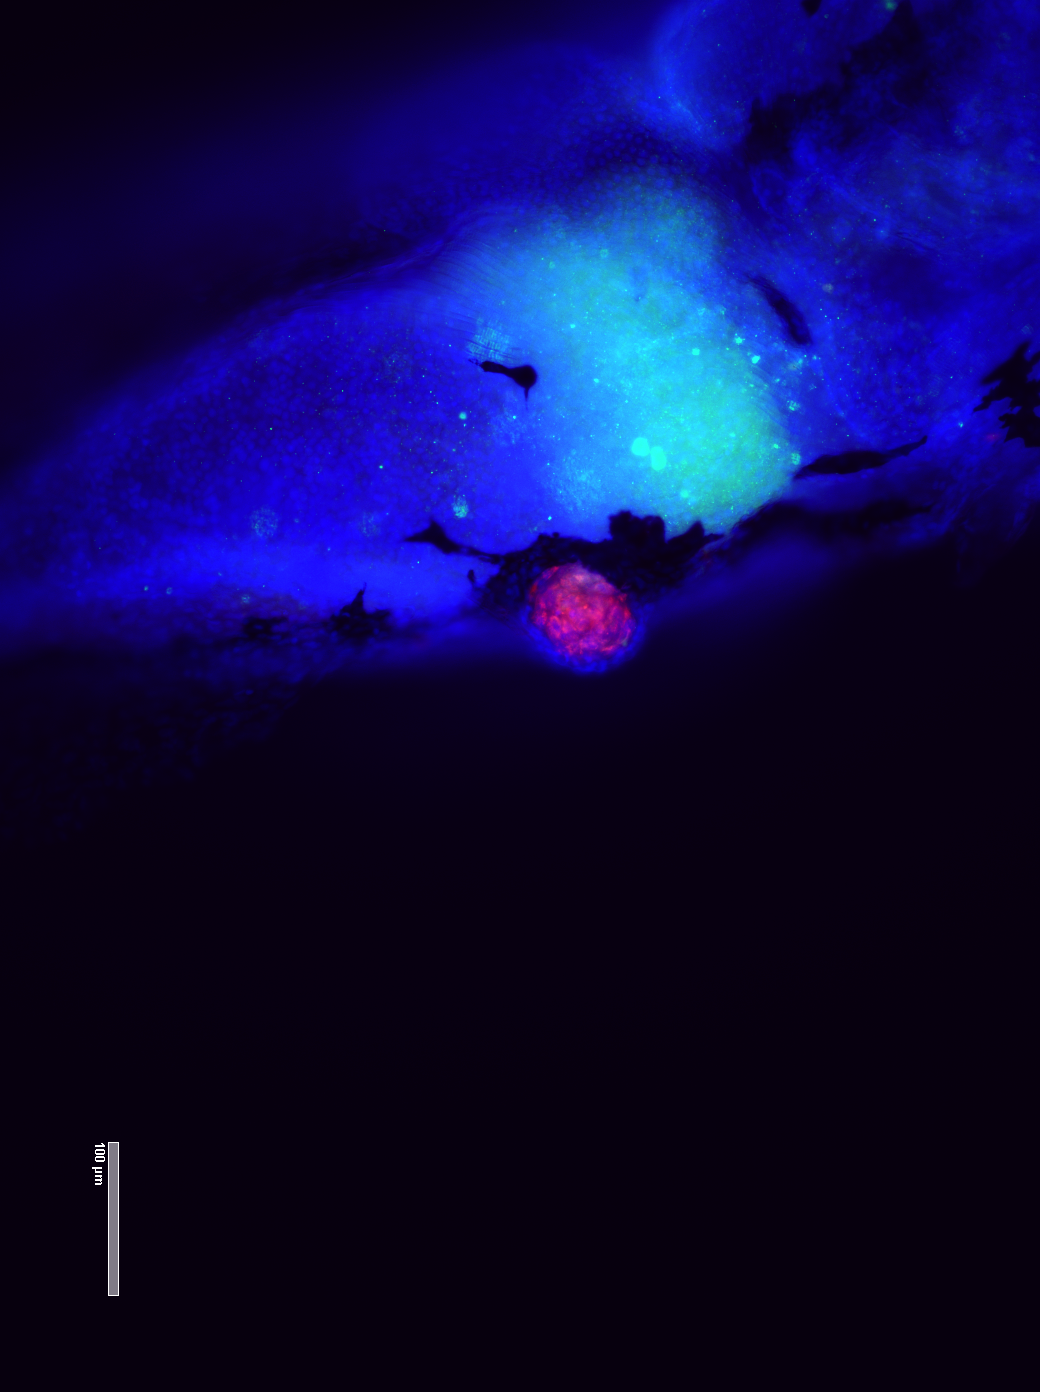

Attēlā aizkuņģa dziedzera audzēja šūnu ksenotransplantāts. Ar sarkanu ir iezimēti mitohondriji, kas palīdz identificēt cilvēka izcelsmes šūnas.

Optimizēts protokols ksenotransplantātu šūnu iezīmēšanai un nervu aksonu iezīmēšanai.

Sagatavots metodoloģiskais apraksts aizkuņģa dziedzera ksenotransplantātu veidošanai un šūnu iezīmēšanai lai identificētu ksenotransplantātos cilvēka šūnas un apoptozi.